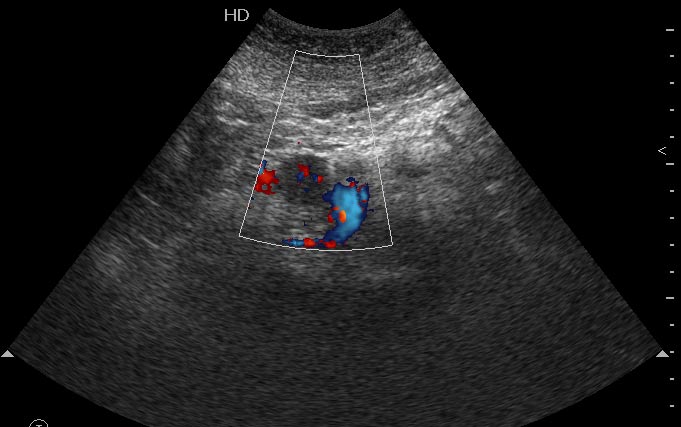

Женщина средних лет, боли в эпигастральной области. На УЗИ выявлено гипоэхогенное образование в области перешейка. Вирсунгов проток слегка расширен. При ЦДК в образовании определяется воспроизводимый кровоток.

Сонограмма панкреас, ее продольное сканирование.